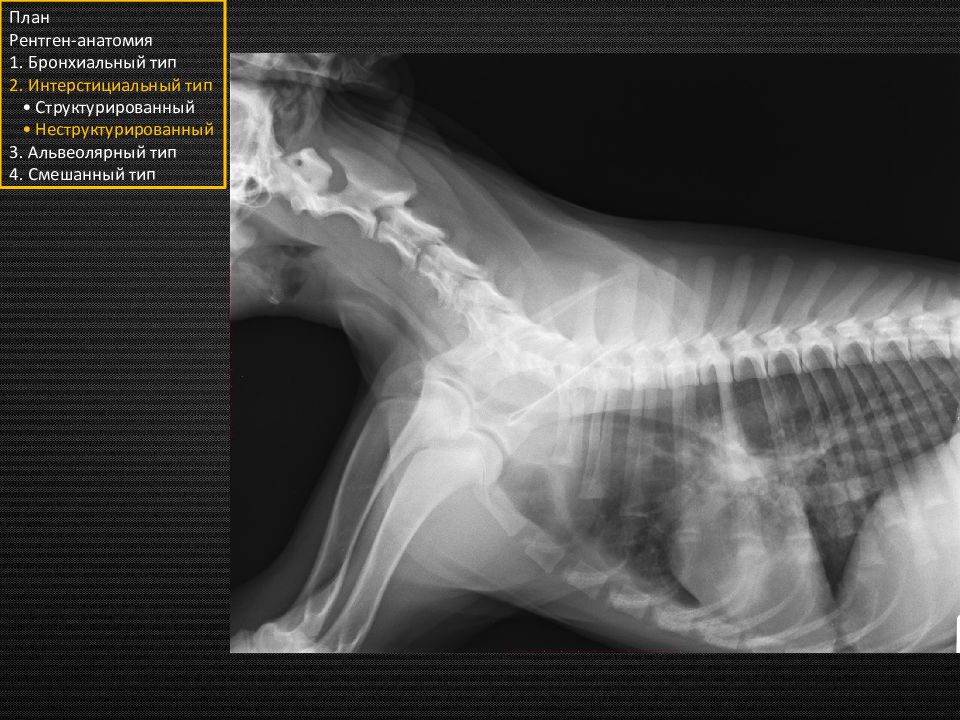

Этот подтип назван неструктурированным, так как не имеет чётких границ и неоднороден. То есть будут некоторые затемнения в лёгких, через которые мы будем видеть долевые сосуды, кости, сердечный силуэт и прочие структуры. План Рентген-анатомия 1. Бронхиальный тип 2. Интерстициальный тип • Структурированный • Неструктурированный 3. Альвеолярный тип 4. Смешанный тип «туман» «вата» «облака»